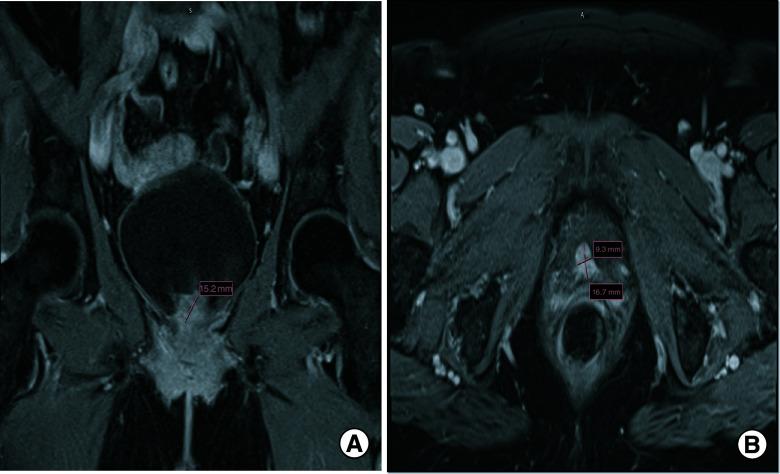

Primary malignant melanoma of the genitourinary tract is extremely rare. We present two such cases in elderly Caucasian females. An 81-year-old female with urinary retention and polypoid urinary bladder mass and a 72-year-old female with gross hematuria and urethral caruncle. After thorough evaluation, they were both eventually diagnosed with primary urogenital melanoma (SOX10 and MART1-positive in tumor cells). In both cases, the presence of melanoma-- and absence of primary melanoma in other sites were consistent with primary urogenital melanoma. Immunotherapy with PD-1 inhibitors and use of neoadjuvant and adjuvant treatment are promising, as treatment guidelines remain unclear and overall survival is low. Additional clinical reporting of primary urogenital melanomas can help in better understanding and ultimately treating it.